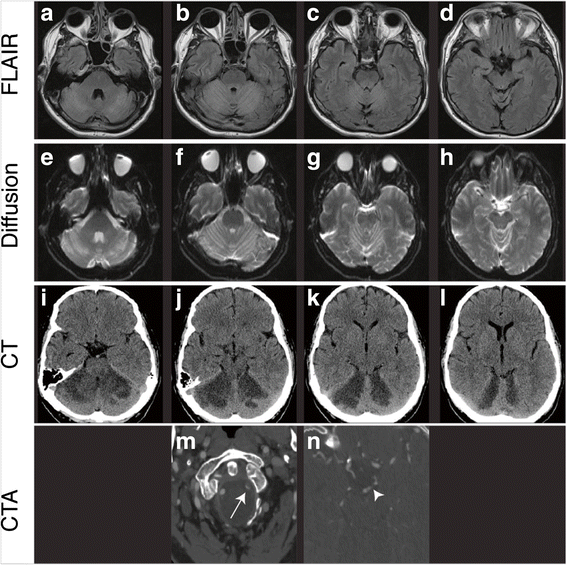

Axial 1.5 T MR, CT and CTA images demonstrate bilateral SCA infarct and left vertebral artery dissection. a–d Sequential axial FLAIR MR images demonstrate bilateral cerebellar hemisphere hyperintensity superiorly with relative sparing inferiorly (not shown) and involvement of the colliculi in the midbrain and the superior cerebellar peduncles. e–h Sequential axial diffusion MR images demonstrate restricted diffusion in both cerebellar hemispheres in the same distribution of the FLAIR images. i–l Sequential axial non-contrast CT images demonstrate patchy areas of hypoattenuation bilaterally in the superior aspects of the cerebellar hemispheres. m–n Select axial CTA images demonstrate decreased caliber of left vertebral artery with arterial lumen filling defect (arrow). As well a filling defect is present in the basilar terminus extending to the P1 segment of the left PCA (arrowhead). MR magnetic resonance, FLAIR fluid-attenuated inversion recovery, CT computer tomography, CTA computer tomography angiography, SCA superior cerebellar artery, PCA posterior cerebral artery